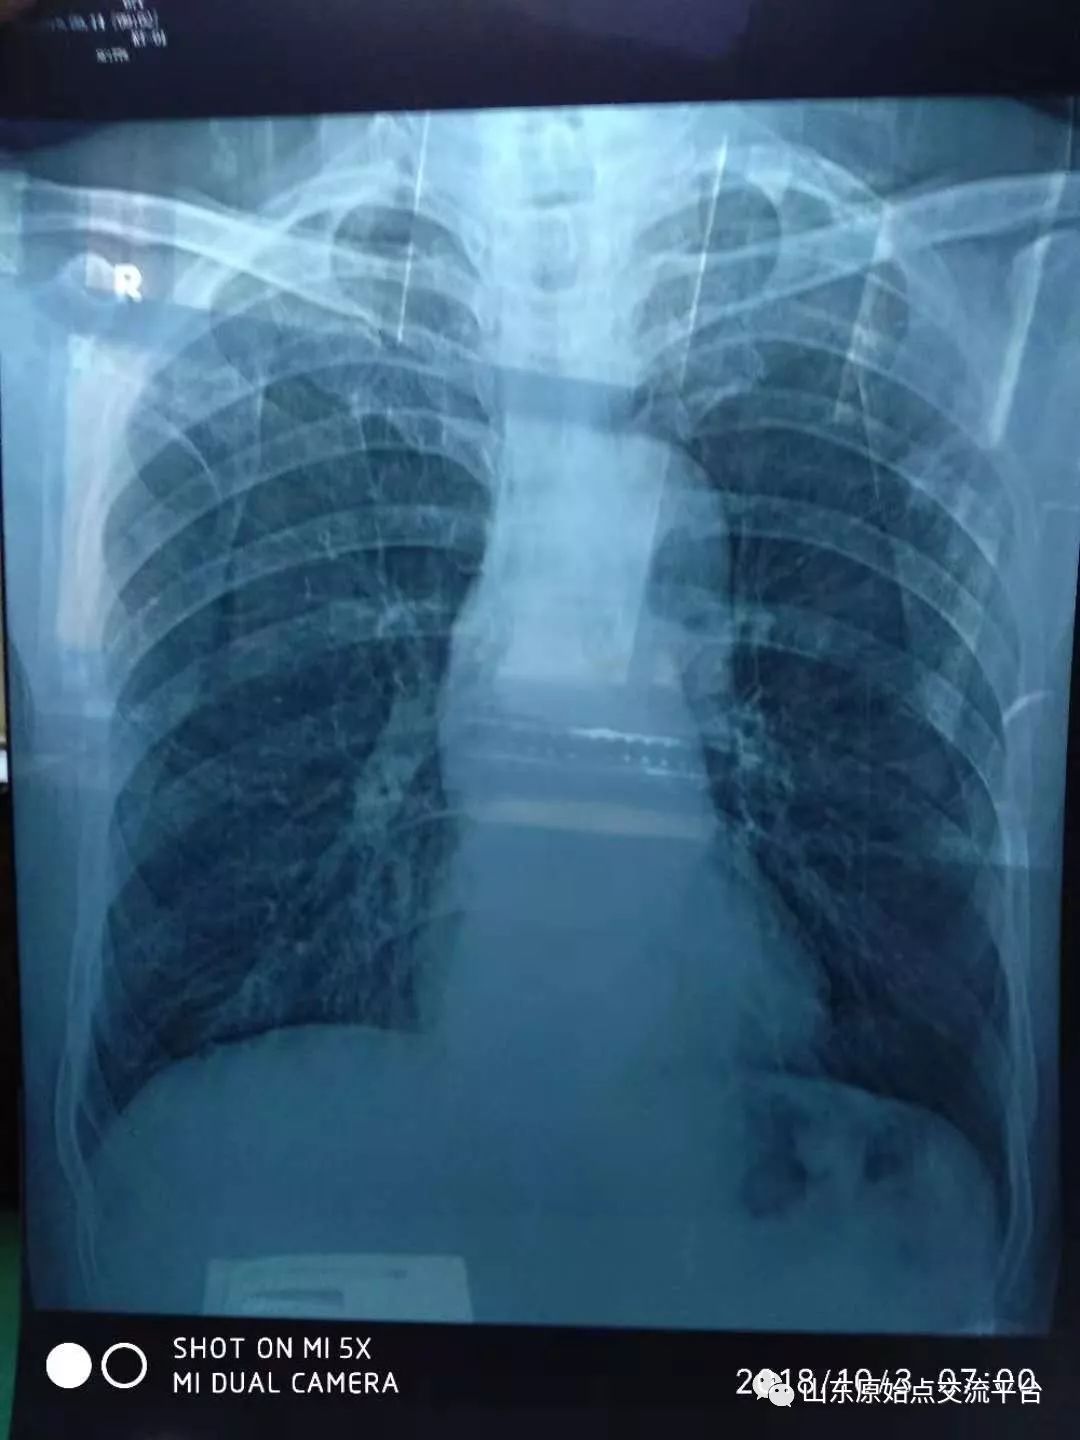

今年9月份为看看恢复情况,我夫人要我拍个片,取了片子医生说你以前得过肺结核,我说沒有啊,他说你得过可能你沒在意,我这时和医生说了实情,去年这时在京协和医院查出的我在手机上存的证件,他不信,癌腫瘤能好,问我怎么治疗的,手术或吃什么药,我说我爱人用原始点给调理的,医生难以置信。我非常高兴说明我已经全好了啊!